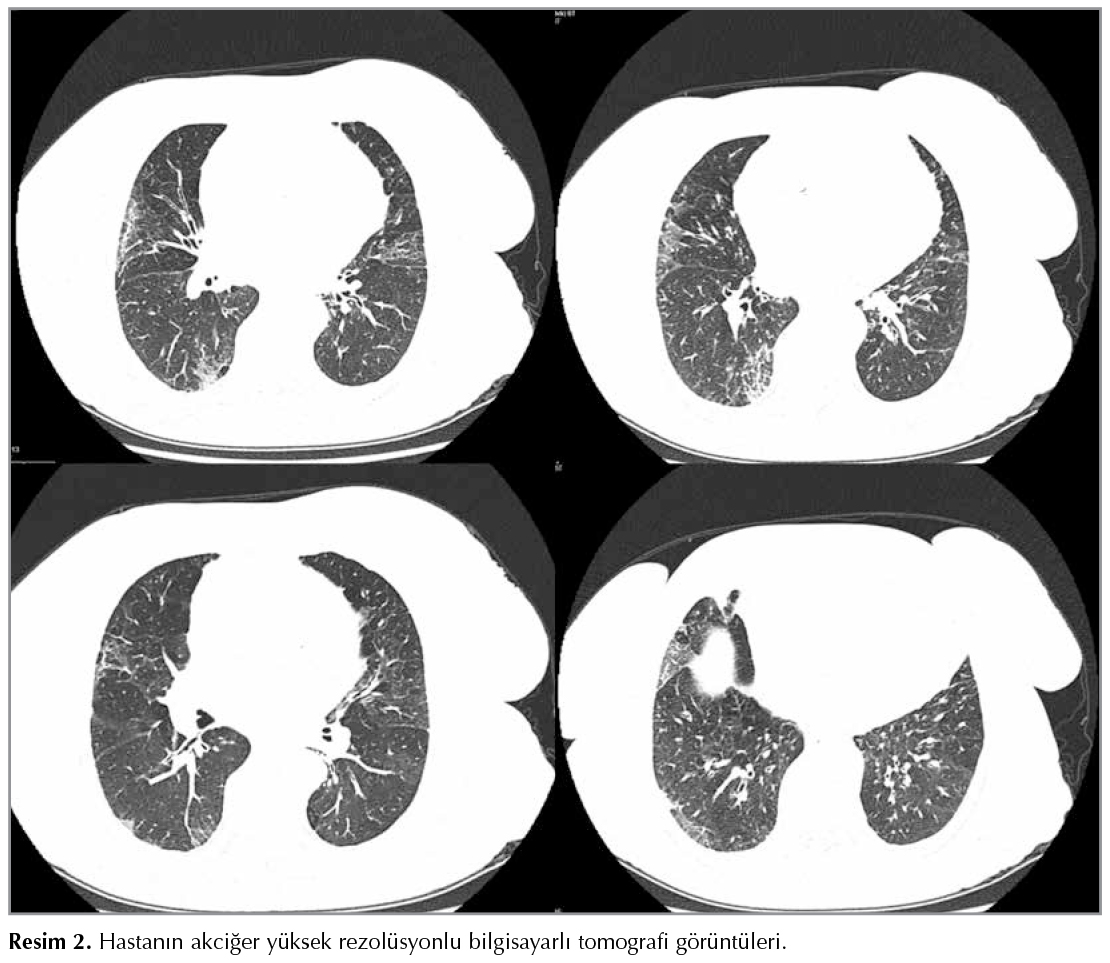

Bu makalede, sekonder tipe dahil olan ve tanı kriterlerini kapsayan IgG4 ilişkili hastalığa bağlı geliştiğini d?ş?nd?ğ?m?z hemofagositik sendrom tanısı alan bir olgu sunulmuştur. Hastanın ge?miş ?yk?s?nde ge?irilmiş idiyopatik pankreatit atağı, septal kalınlaşmayla giden yer yer buzlu camlarla karekterize dif?z interstisiyel akciğer hastalık varlığı, kemik iliği biyopsisinde plazmasitozis ile uyumlu g?r?nt?, y?ksek kan IgG4 d?zeyleri nedeniyle hemofagositik sendrom tanısı almıştır (Şekil 2A ve Şekil 2B). Literat?r değerlendirmelerinde Umahara ve arkadaşları IgG4 ilişkili hastalık i?in tanı kriterleri oluşturmuştur (4). Buna g?re kesin (definite), muhtemel (possible), olası (probable) tanılar şeklinde ayrılabilir. Bu tarifte diğer spesifik organ tutulumları akut idiyopatik pankreatit, renal yetersizlik ve Mickulik disease olarak tanımlanmıştır. Bizim hastamız da ilk tanı aldığı d?nemde bir akut pankreatit atağı ge?irmiştir ve bu tablonun muhtemel (possible) kısmında yer almaktadır. Akciğer ilişkili IgG4 hastalığında ise radyolojik olarak, solid nod?ler tip, yuvarlak şekilli buzlu cam opasite tipi, alveolar interstisiyel tip ve bronkovask?ler tip şeklinde tanımlamalar yapılmıştır (Resim 2) (5). Bizim olgumuzda interstisyel akciğer hastalığı nedeniyle uzun s?re değişik dozlarda ve ?eşitte imm?ns?presif tedavi almış olması, laboratuvar ve klinik bulgularıyla ?ncelikle sepsis d?ş?n?lm?şt?r. Takiplerinde pansitopeni, diren?li ateş, hepatosplenomegali, ferritin y?ksekliği, total bilirubin y?ksekliği gibi bulgular nedeniyle ?ncelikli olarak hemofagositik sendrom d?ş?n?lm?şt?r. Hastada y?ksek kanama riski olması, diğer bulguların g??l? bir şekilde hemofagositik sendrom d?ş?nd?rmesi nedeniyle bu d?nemde kemik iliği aspirasyonu yapılamamıştır. Tekrarlayan seferlerde yapılan periferik yayma ile de akut l?koz yapabilen bir maliginite varlığı dışlanmıştır. Hemofagositik sendrom, doğal katil h?crelerdeki defekt ve aşırı makrofaj aktivitesi sonucu oluşan hayatı tehdit eden hiperinflamatuvar ?l?mc?l bir hastalıktır (6). İsve?'te 0.12/100.000, Japonya'da 0.342/100.000, T?rkiye'de ise 7.5/10.000 g?r?ld?ğ? bildirilmektedir (2). Primer (ailesel) ve sekonder (infeksiyonlara bağlı) olmak ?zere iki tipi olmasına rağmen klinik bulgular aynıdır. Ateş, hepatosplenomegali, pansitopeni sık g?r?l?r. Ferritin seviyesi > 500 μg/L olan 330 olgunun incelediği ?alışmada > 10.000 μg/L ferritin değerlerinde tanının %90 duyarlı %96 ?zg?l olduğu, > 30.000 μg/L değerlerinde ise %100 ?zg?l olduğu bildirilmiş (6). Bizim olgumuzda da ferritin değerleri en y?ksek 22.000 μg/L seviyesini g?rm?şt? (hastalık ilişkili tanı kriterleri Tablo 1'de sunulmuştur) (6,7).

Resim 2